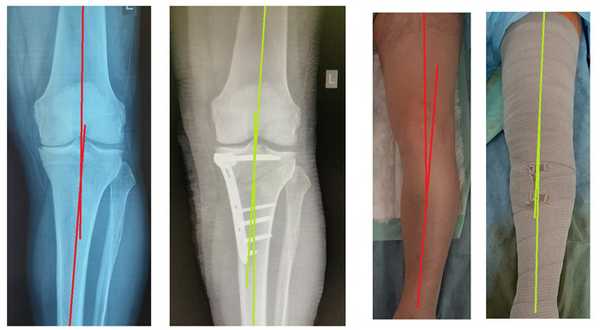

![лечение артроза коленного сустава, корригирующая остеотомия]()

В результате операции восстанавливается нормальная ось нижней конечности и нагрузка перераспределяется на сохранные наружные отделы сустава. Сразу же после операции видно изменение оси конечности, на рентгенограммах определяется коррекция оси из варуса в небольшой вальгус и хорошо видно как раскрывается разгруженная внутренняя щель коленного сустава.